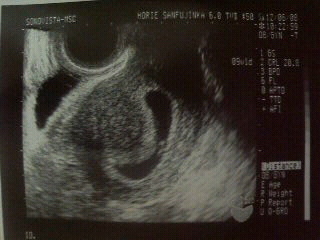

妊娠 8週目- 1 妊娠8週目(6日目)のお腹の大きさを大公開 11 妊娠初期から生理前の様なお腹の痛みが気になる 2 妊娠8週目の赤ちゃんの大きさ、作られる器官、成長の様子など 21 受精してから妊娠9週目までの赤ちゃんの成長の様子(動画)8週3日!!CRL176㎜♡ 大きさ的には8週5日の大きさ(*^^*) 順調に大きくなってる(*´艸`) 小さい小さい赤ちゃん♡ 少し手足を動かしてる姿も見れました♡ 母子手帳も貰ってきて、 次は2週間後(*ovv)o 毎日エコーの時に撮った動画を見ながら、 過ごそうと思います♡ 予定日12月28日♪

妊娠8週4日 8w4d の超音波 エコー 写真

妊娠8週目 8w0d 6d のエコー写真とエピソード 妊娠3ヶ月 Cozre コズレ 子育てマガジン

妊娠8週 3 6日 のエコー写真 体験談

妊娠8週目のエコー写真 1 4cmまでに成長 頭殿長 とうでんちょう とは 初めての妊娠 赤ちゃんはリアルタイムで成長している ブログ